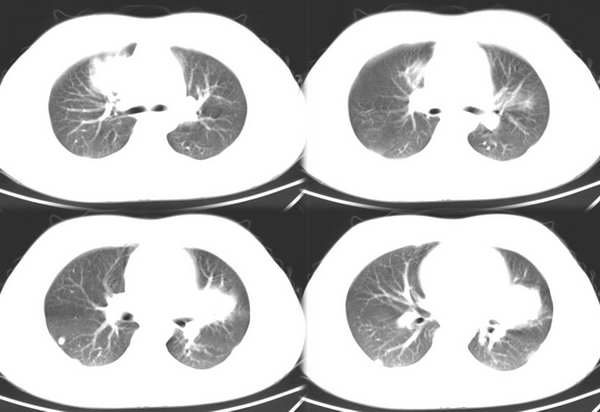

男,18岁。咳嗽,胸闷4天。

肺转移